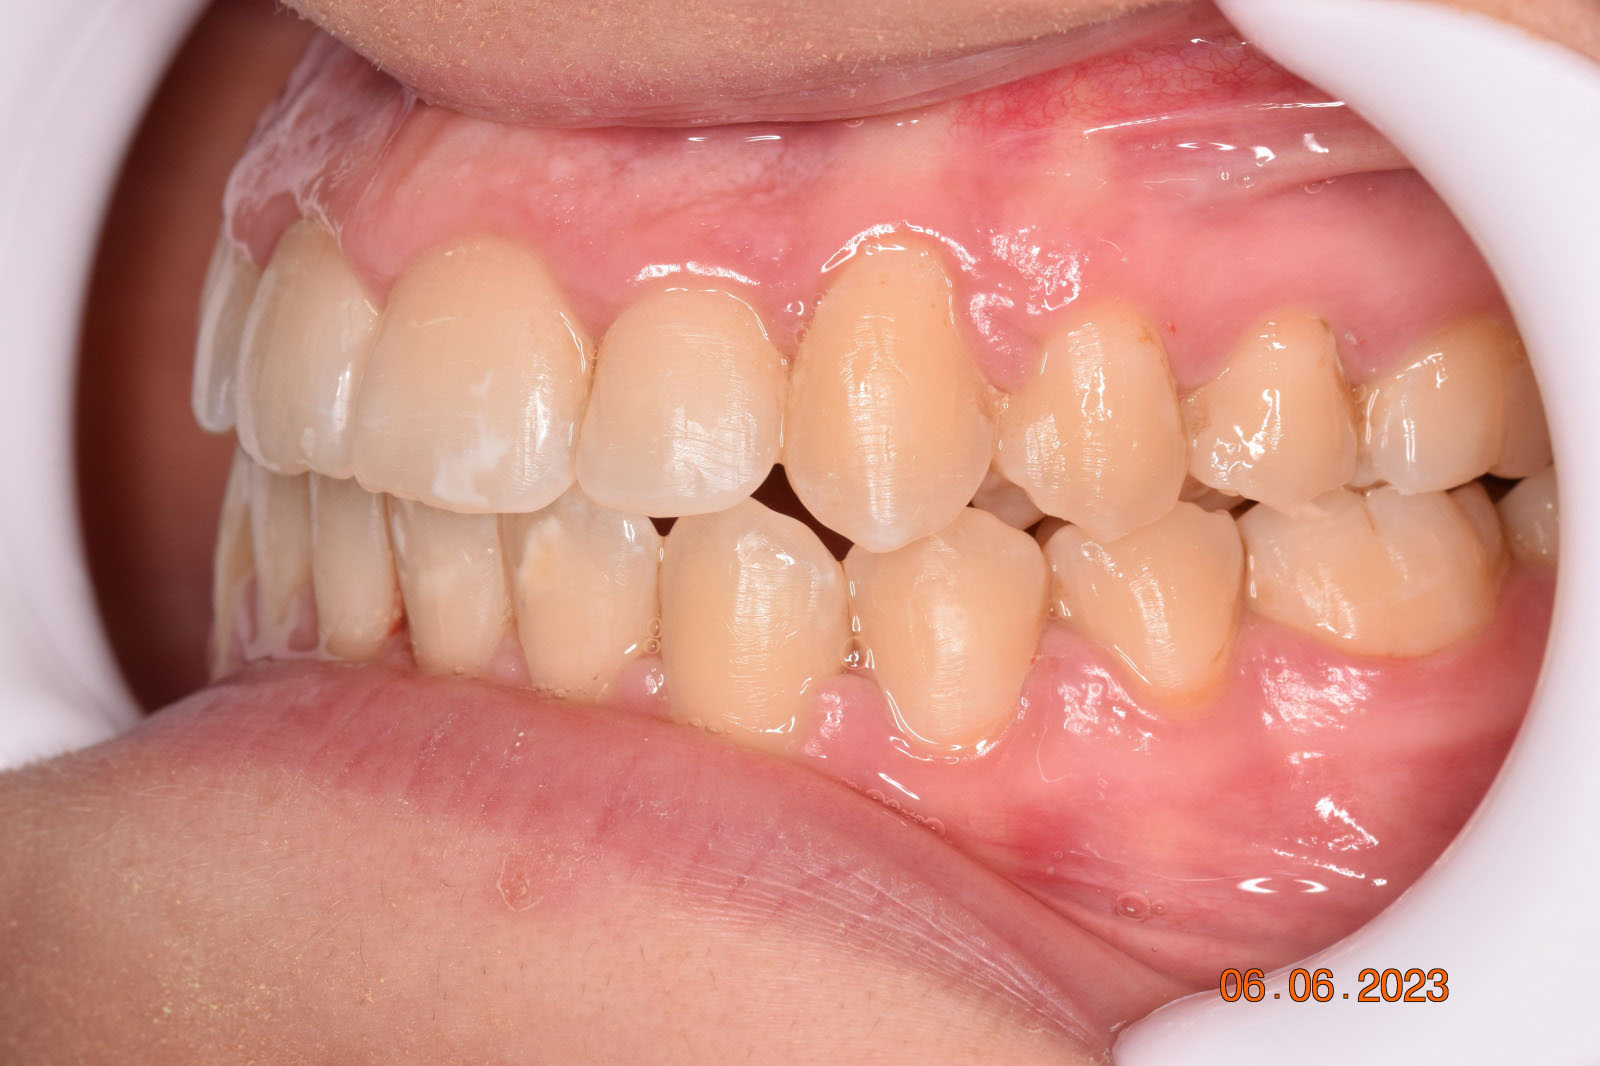

A 27-year-old female patient presented with class III malocclusion, 15 mm crowding in the upper arch, an anterior open bite, a lateral crossbite, and a total ABO score of 29. Her facial profile was straight with a retrusive maxilla, and the upper and lower incisors were retroclined. An extreme lack of midface support was also noted, and the constricted dental arches resulted in a poor smile width and dark buccal corridors. No myofunctional investigations were performed at the time, as they were initially considered unnecessary.

Adhering to the principles of Face First Orthodontics, the primary objective was to increase midface support by expanding the upper maxilla, fixing the cross bite, and aligning the teeth. Closing the open bite was a secondary objective.

The treatment began in 2017. Given the patient’s preference for less visible brackets, Damon Clear brackets were selected. High torque upper cuspids and low torque upper incisors were chosen to offer the best torque control for upper arch development. For the lower arch, there were no alternative bracket configurations available. Bite turbos were applied to the upper second molars.